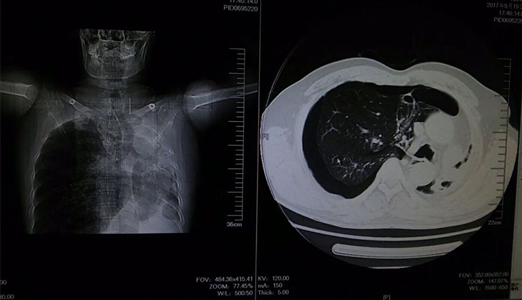

该患者为中年男性,胸闷,气促,休息后症状无缓解,来院就诊时全身大汗淋漓,口唇发紫,呼吸困难。临床医学院/附属医院医生询问病史后,发现该患者病情较复杂,且患者及家属对既往病史情况不太了解。考虑情况危急,当班医师立即组织抢救,给予吸氧、建立静脉通路及行胸部CT,同时请胸外科医师急会诊。经详细检查后,发现患者右肺自发性气胸,如不及时救治将危及生命。医务人员立即为患者做了右胸腔穿刺排气抢救,后给予胸腔闭式引流。在全体医护人员一个多小时的努力下,患者病情得到缓解,患者及家属对临床医学院/附属医院医务人员的精湛医术表示感谢。

张力性气胸来势凶猛,若抢救和处理不及时,则会危及生命。急诊科患者往往病史不详,且病史复杂多变、危及生命,带给医院及医生极大的考验。疾病的诊治需要多科室密切协作、相互补充,多学科齐心协作,才能最大限度提升救治水平,保障诊治效率和质量。该患者的抢救成功,体现了临床医学院/附属医院急诊科及心胸外科医护人员的快速反应能力和实践操作能力,同时也充分体现出多学科协作在急危重症抢救中的巨大作用。